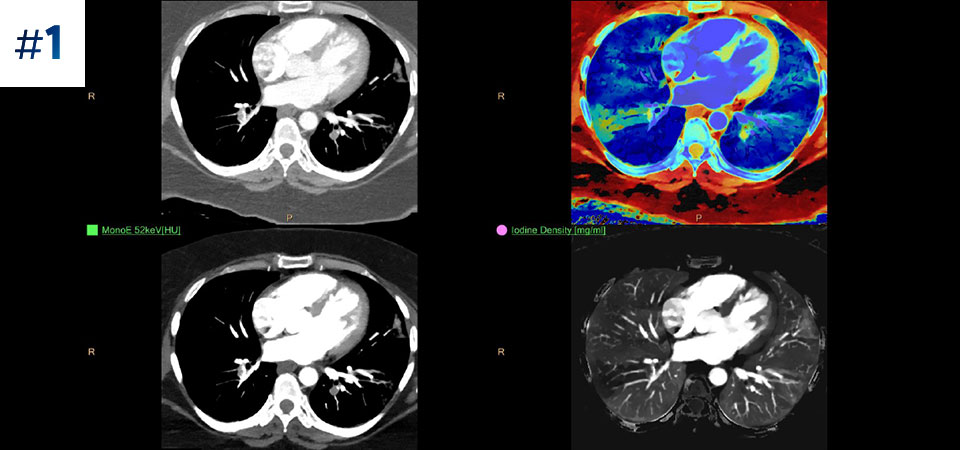

Neck mass

See the difference between spectral-detector CT and conventional CT

Learn about the advantages of spectral-detector CT